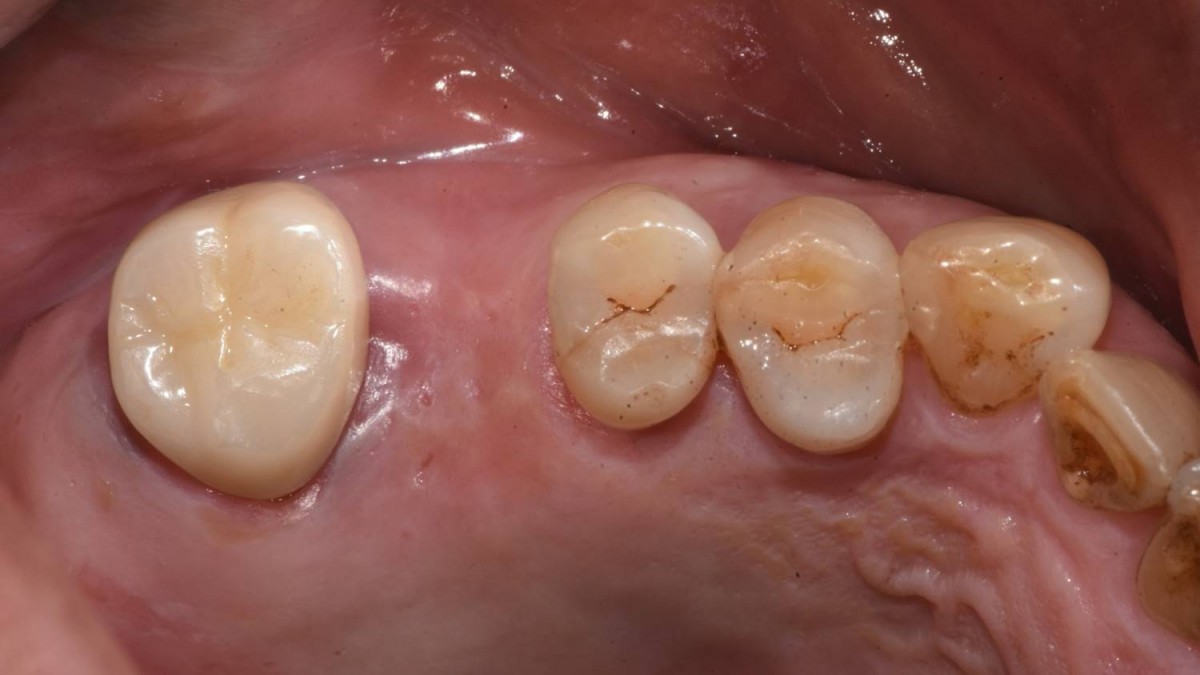

<GCaks> A 56-year-old male patient had pain-inducing caries, and perio-involved tooth mobility resulted in a tooth fracture at 1st molar. And it was removed months ago. He was a heavy smoker and showed poor oral hygiene.